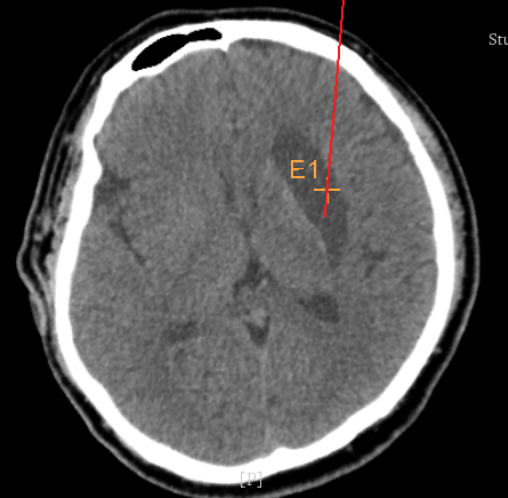

實(shí)際手術(shù)時(shí),機(jī)器人在幾分鐘內(nèi)就完成了空間注冊(cè),機(jī)械臂在定位儀的引導(dǎo)下自動(dòng)定位,準(zhǔn)確鎖定靶點(diǎn)。

術(shù)前韓帥醫(yī)生使用“睿米”制定手術(shù)規(guī)劃

手術(shù)規(guī)劃在機(jī)器人軟件上制定完成